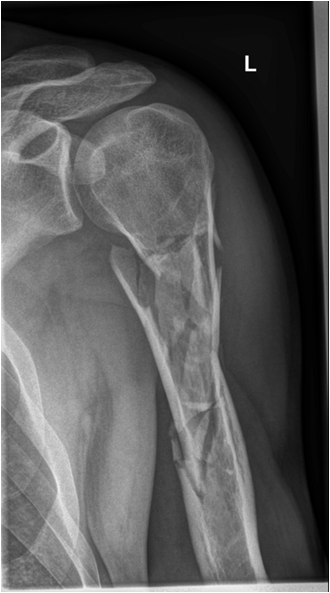

Fig. 8. Diagram showing different types of fractures: fissure or incomplete fracture, transverse simple fracture, oblique simple fracture, spiral fracture, simple and complex comminuted fracture. The x-ray example shows a severely comminuted fracture of the proximal humerus. Note that the angulation of the facture with 30-degree dorsal tilt of the distal fragment is fully seen only on the transscapular view (second plane).